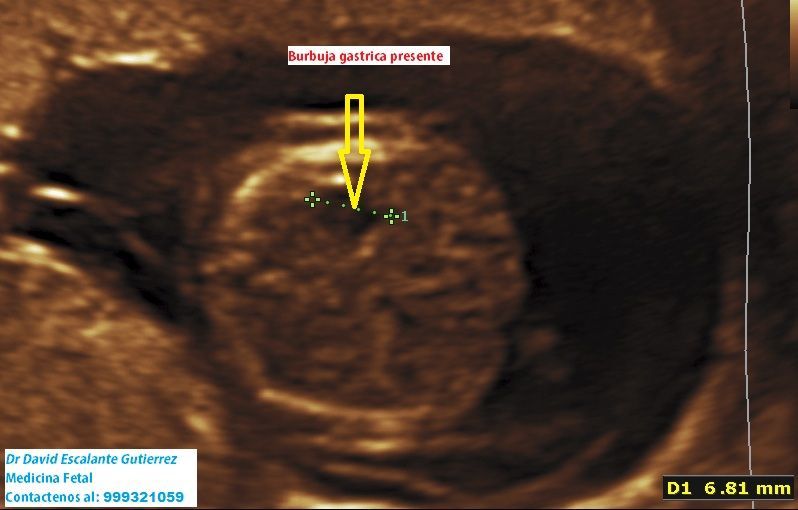

Realizamos las ecografías de viabilidad del embarazo, genética, morfológica, de bienestar fetal, ecocardiografías fetales, así como procedimientos invasivos como biopsia de vellosidades coriales y amniocentesis.